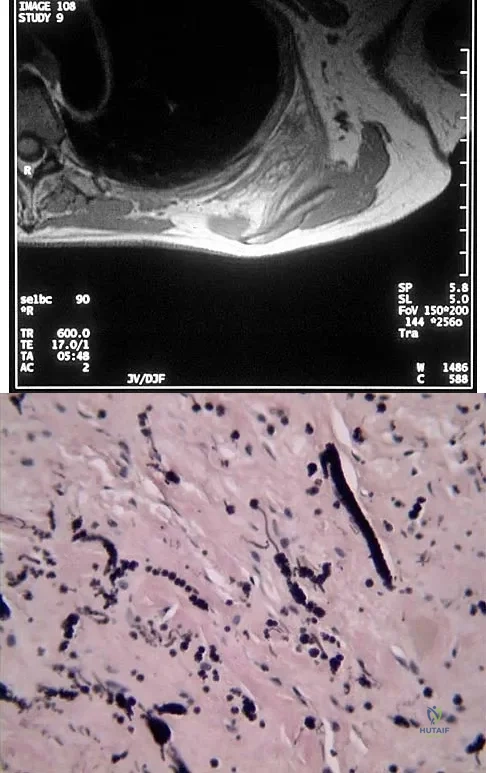

Explanation

Question 83

A 58-year-old woman has had a painless periscapular mass for the past year. An MRI scan and biopsy specimen are shown in Figures 4a and 4b. What is the most likely diagnosis?

Explanation